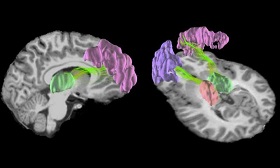

پژوهشگران در این مطالعه از روش ام.آر.آی برای اسکن مغز ۱۶ دانش آموز دبیرستانی ۱۵ تا ۱۷ ساله استفاده نمودند.

آنها مغز دانش آموزان را پیش و پس از یک سال فوتبال بازی کردن، اسکن کردند.

پس از اسکن، پژوهشگران متوجه تغییرات قابل ملاحظه ای در ساختار ماده خاکستری در جلو و عقب مغز شدند.

آنها دریافتند تاثیرات بسیاری در ساختار ماده خاکستری و همچنین ساختار عمیق داخل مغز رخ داده است.

محققان با استفاده از یک نوع جدید از ام.آر.آی به نام "diffusion kurtosis imaging" برای بررسی عصب پیچیدهای که ماده خاکستری را تشکیل میدهند، استفاده کردند. آنها دریافتند که سازماندهی ماده خاکستری در مغز بازیکنان پس از یک سال فوتبال بازی کردن، تغییر کرده است.